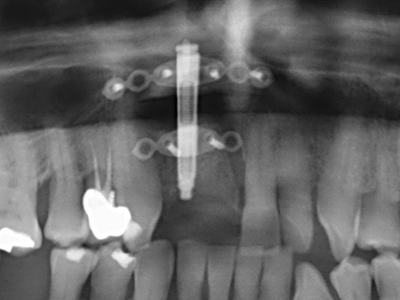

Fig. 11: The postoperative panoramic image shows the vertical augmentation and sinus floor elevation.

Fig. 12: After six months of healing, the alveolar ridge is vital and sufficiently dimensioned in all planes.